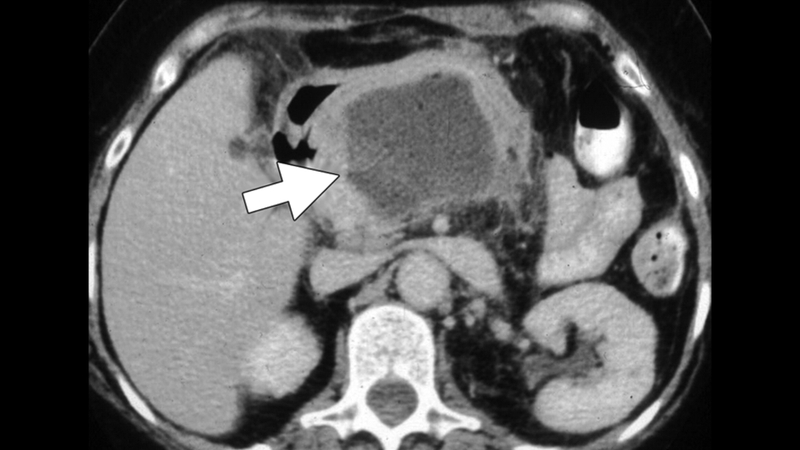

Dưới đây là hình ảnh CT tĩnh mạch cửa bụng của một phụ nữ 75 tuổi bị viêm tụy cấp có nhiễm trùng huyết nặng. Có khối u giảm đậm độ thay thế cổ tụy (mũi tên) bằng mô mỡ quanh tụy. Lưu ý thành dày bao quanh khối u, chọc hút xác nhận đây là áp xe.

Hình ảnh CT tĩnh mạch cửa bụng của một phụ nữ 75 tuổi bị viêm tụy cấp có nhiễm trùng huyết nặng